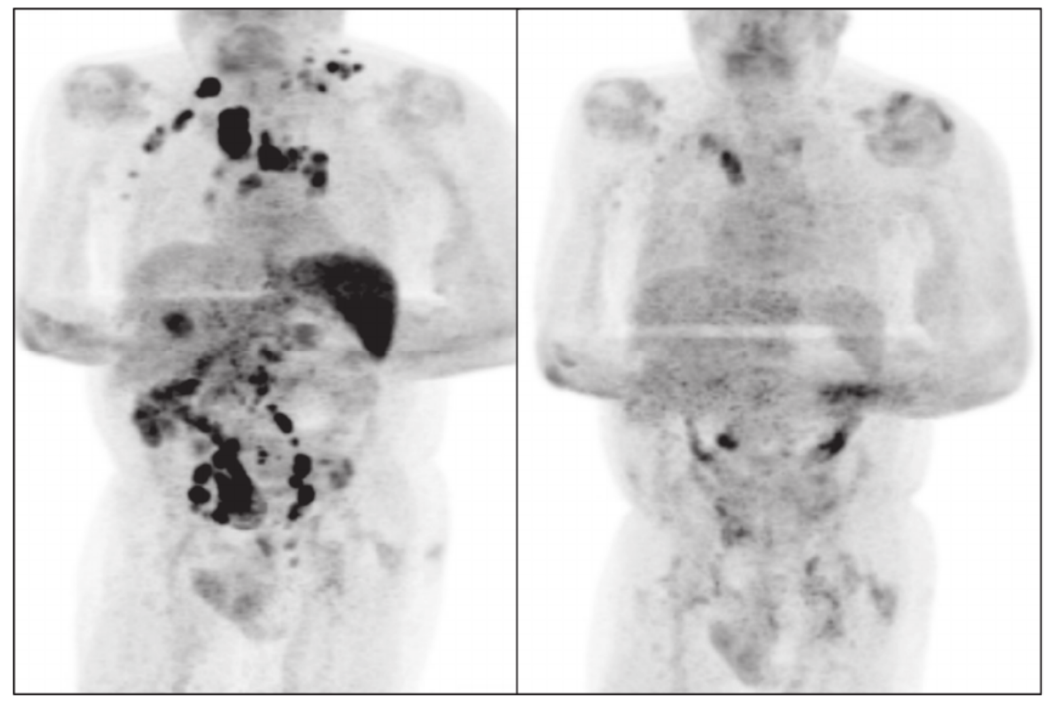

大千世界无奇不有!此前,《英国血液学杂志》(British Journal of Haematology)曾报道了一个匪夷所思的案例:一位霍奇金淋巴瘤患者感染了新冠病毒,四个月后,他体内的肿瘤竟几乎消失了。在患者不幸“中招”的过程中,其未接受皮质类固醇和免疫化疗。

左图:黑色区域显示感染新冠前癌细胞已扩散至全身多处器官

非也!研究人员推测,可能是感染新冠病毒触发了患者体内的抗肿瘤免疫反应,激活的免疫系统成功清除了体内的癌细胞。换言之,这是一个通过感染病毒来杀死癌细胞的故事,并非绝对意义上“躺平”就能发生的“医学奇迹”。